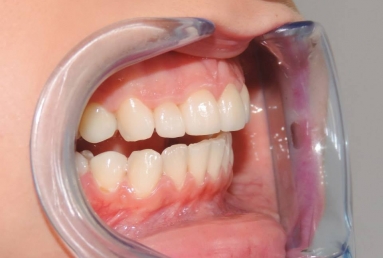

Very small lateral incisors covered with full ceramic crowns and ceramic veneers on central incisors. The prosthetic space was correctly split between the four incisors, in order to reduce the disproportion between the large centrals and the very small laterals. The preparation of the teeth was minimally invasive, all four incisors remained vital.